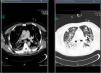

Treatment with linezolid was maintained and the remaining antimicrobials were discontinued. Steady state plasma concentrations of linezolid were determined from the third day of treatment using a high-performance liquid chromatography technique, with a minimum plasma concentration state (Cminss) (or pre-dose) of 0.8mg/L and maximum (Cmaxss) (at the end of infusion) of 4.8mg/L, which were considered subtherapeutic (therapeutic range Cminss>2mg/L). Although blood cultures became negative on the fifth day of treatment, the patient showed a protracted respiratory clinical course with worsening of radiographic images, and according to drug susceptibility testing, antimicrobial coverage was expanded with intravenous clindamycin (600mg every 8h) and ciprofloxacin (400mg every 8h). In addition, the dosing interval of linezolid as well as the duration of the time of infusion were modified on several occasions based on results of plasma drug concentrations in order to achieve an optimal pharmacokinetic (PK) and pharmacodynamic (PD) ratio (Table 1). Seventeen days after starting treatment with linezolid, therapeutic levels were reached with a regimen of 600mg every 8h administered in continuous infusion, which coincided with eradication of PVL producing MRSA in pulmonary samples. Thoracic computed tomographic (CT) scans performed over the course of treatment revealing extensive involvement of the pulmonary parenchyma with multiple cavities and important necrotic areas in the upper lobes compatible with pneumatoceles and bronchiectasis (Fig. 1). The patient required mechanical ventilation during 73 days (with tracheostomy) with procedural sedation, analgesia, and prolonged muscle relaxation. After 5 weeks of treatment with linezolid, the patient was successfully weaned. Linezolid was administered for a total of 35 days, clindamycin for 29 days and ciprofloxacin for 19 days. He was discharged after a 3-month hospitalization. At the present time, his oxygen saturation on room air is >95%.